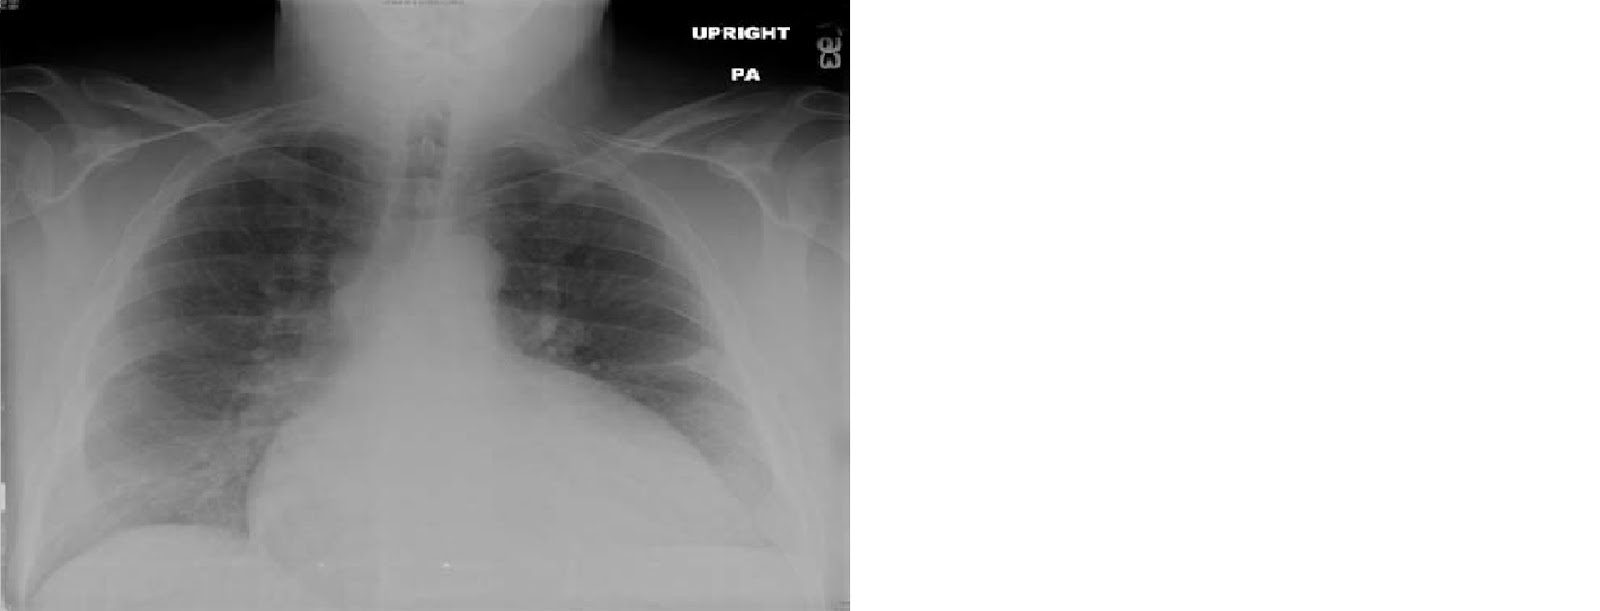

A 74-year-old man who is a chronic smoker presents with fatigue and shortness of breath. He has not seen a physician for many years and says he has been basically healthy.

On physical examination, he is found to be pale, mildly cachectic, and his lips are cyanotic.

His breath sounds are distant, although crackles can be heard in both lung bases. His heart sounds are best heard in the epigastrium; and a third heart sound is present. He has mild peripheral edema.

His resting pulse oximetry is 74%.

The chest X-ray (CXR) shows emphysema and his echocardiogram confirms heart failure.

The X Ray is shown below: